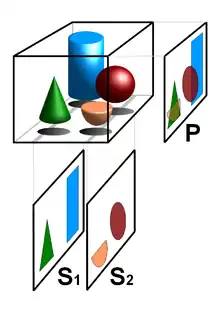

Creation of three-dimensional images

Volume rendering techniques have been developed to enable CT, MRI and ultrasound scanning software to produce 3D images for the physician.[24] Traditionally CT and MRI scans produced 2D static output on film. To produce 3D images, many scans are made and then combined by computers to produce a 3D model, which can then be manipulated by the physician. 3D ultrasounds are produced using a somewhat similar technique. In diagnosing disease of the viscera of the abdomen, ultrasound is particularly sensitive on imaging of biliary tract, urinary tract and female reproductive organs (ovary, fallopian tubes). As for example, diagnosis of gallstone by dilatation of common bile duct and stone in the common bile duct. With the ability to visualize important structures in great detail, 3D visualization methods are a valuable resource for the diagnosis and surgical treatment of many pathologies. It was a key resource for the famous, but ultimately unsuccessful attempt by Singaporean surgeons to separate Iranian twins Ladan and Laleh Bijani in 2003. The 3D equipment was used previously for similar operations with great success.